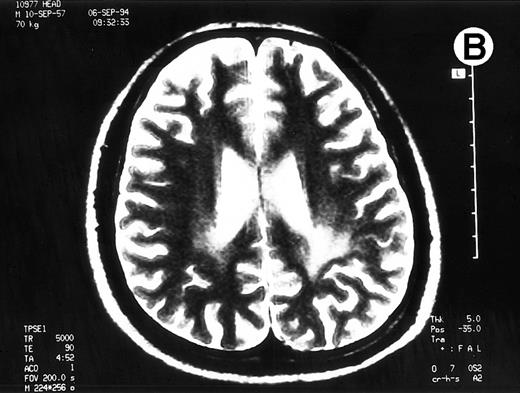

Paths of blight signal on T2-weighted MRI in white matter of brain adjacent bilateral posterior lateral ventricles. (A) On day 526 when we just withheld cyclosporine. (B) On day 698 when chronic GVHD resolved by readministration of cyclosporine.

A 35-year-old man with a chronic myelocytic leukemia in a first chronic phase received an allo-BMT prepared for cyclophosphamide 120 mg/kg and total body irradiation 12 Gy from an HLA-identical sibling in October 1992. Acute GVHD developed in grade III and progressed to an extensive chronic GVHD (cGVHD), which included lichenoid lesions of buccal mucosa, oral dryness, keratoconjunctivitis sicca, and hypolacrimation in addition to skin lesion and liver dysfunction. We treated his cGVHD with 150 mg/d of cyclosporine (CsA) and 10 mg/d of prednisolone (PSL). With dose reduction of CsA from 12 months after allo-BMT, his cGVHD gradually deteriorated. Abrupt seizures, lasting a few minutes, developed on day 491 and day 496 when the patient received 100 mg/d of CsA and 10 mg/d of PSL. Neurological examination revealed no abnormalities. MRI detected the pathes of blight signal on T2-weighted method in white matter of brain adjacent bilateral posterior lateral ventricles (Fig 1A). The eloctroencephalogram revealed epileptic abnormal δ and θ waves on left frontal to central lobe. An examination of cerebrospinal fluid (CSF) revealed as follows: an initial pressure 120 mm H2O, protein 98 mg/dL, sugar 55 mg/dL, chrolide 123 mmol/L, cell count 38/μL with all lymphocytes and negative results in antibodies for cytomegalovirus, herpes simplex virus type-1, and toxoplasma. The concentration of interferon-γ was 0.3 U/L in serum and 1.0 U/L in CSF, which measured by radioimmunoassay kit (Medgenics, Belgium).

To rule out the possibility of CsA neurotoxicity, although the trough levels of CsA ranged from 130 to 170 ng/mL, we withheld CsA at day 526. Despite this attempt, the CNS lesions on MRI did not change, and we subsequently restarted 150 mg/d of CsA at day 537. Thereafter, the CNS lesions gradually resolved with 150 mg/d of CsA and 10 to 20 mg/d of PSL (Fig 1B), coinsident with resolution on the other signs of cGVHD. The seizures never recurred with 600 mg/d of sodium valproate. The patient has now minor CNS lesion and mild signs of cGVHD with 100 mg/d of CsA and with 90% of Karnovsky score at 62 months following allo-BMT.